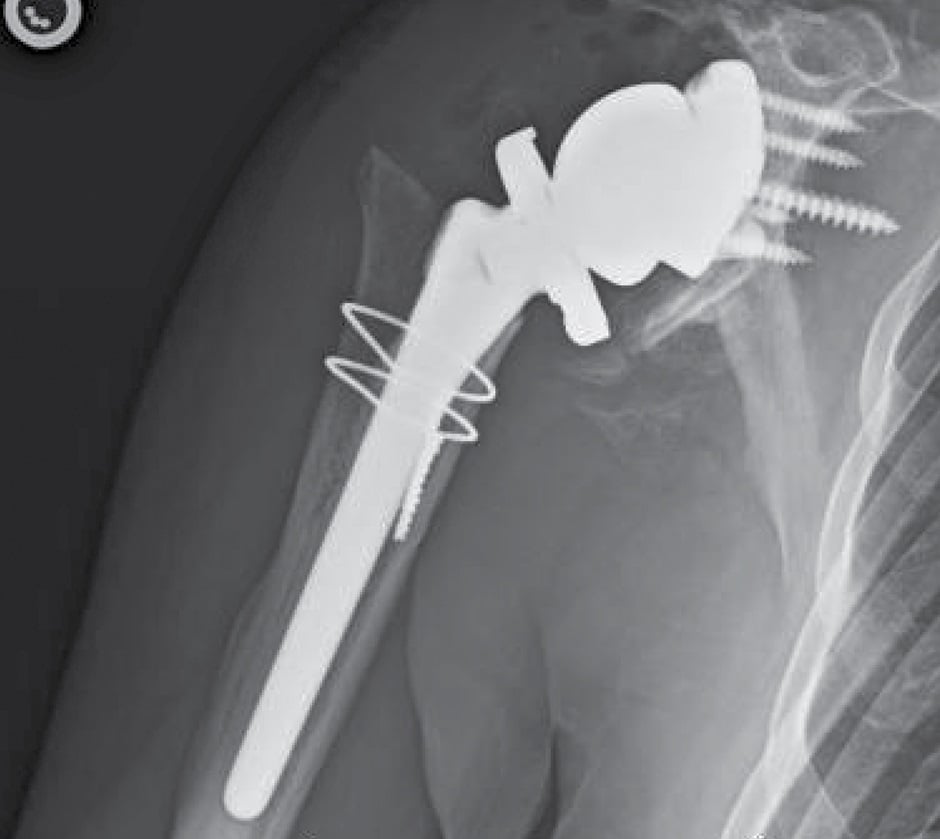

The previous incision was used with a standard deltopectoral approach to place the VRS glenoid baseplate over the anterior rim of the glenoid, which was secured with a central 6.5 × 45 mm nonlocking screw and 4 peripheral 4.75 mm locking screws. A 41 mm glenosphere was impacted onto the taper with maximal offset inferiorly. The humeral bone was deficient from prior osteomyelitis, and 2 cerclage wires were placed to prevent extension of a 2.5 cm cortical defect in the proximal humerus. A 10 × 122 mm cemented humeral prosthesis was implanted in 20° of retroversion with a standard tray and +0 polyethylene. The components were reduced and the subscapularis was repaired with braided nylon sutures.

At 6 months postoperatively, the patient had no pain, a stable implant (Fig. 3), and greatly improved range of motion, with forward elevation to 110° and external rotation to 30°. The implant remains intact and stable 4 years postoperatively.

Figure 3: X-rays at 6 months postoperatively show a stable implant.